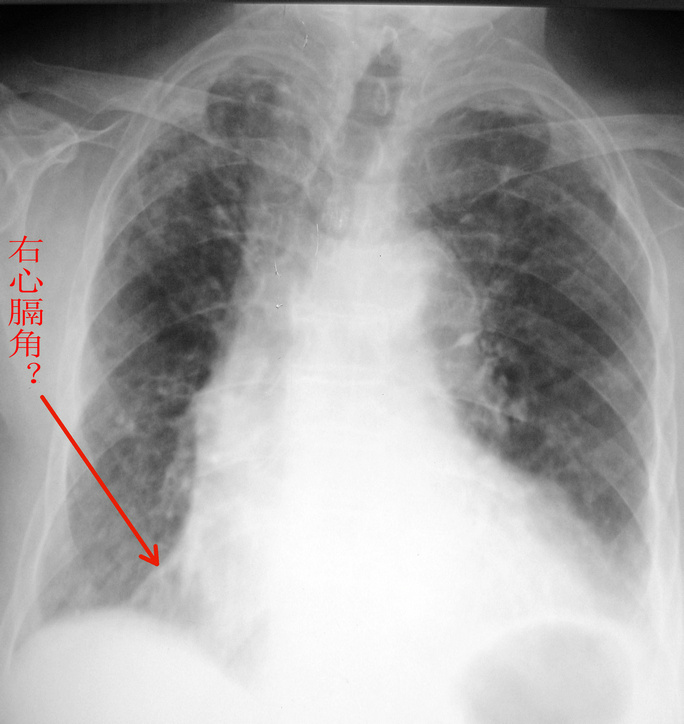

女.80.慢支炎5年.加重1周.请各位会诊

右肺中叶肺不张或阻塞性肺炎+两肺间质纤维化---ct确诊。

右上肺陈旧性肺结核?

慢支炎。 右心隔可能是心包垫。

考虑慢性支气管炎合并感染,右上继发型肺结核。必要时做ct进一步检查。

慢支并感染,双上肺不能排除结核,右心膈角最先应考虑心包脂肪垫。体位不正,气管右偏,是不是病人有些驼背所致?

右上肺可见片结影,余肺纹增多且模糊,支持慢支并感染,右上肺继发性结核。建议ct。